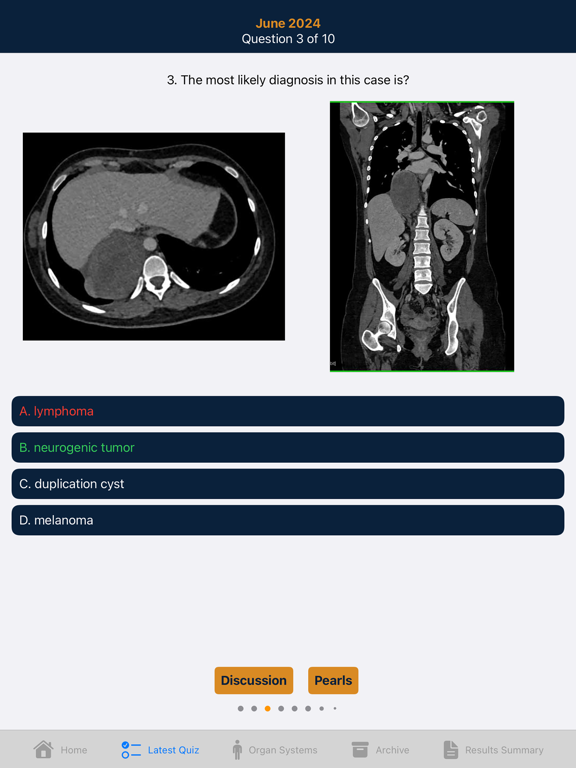

One of the classic formats for learning radiology has always been the quiz.In this application we provide you with our latest innovation in CT education taking advantage of the iPad and iPhone.

It's unique capabilities provide an easy to use environment that combines images , text and sound to enhance the learning experience. Over 1800 cases in 15 different categories that include case specific pearls and an audio discussion of the case.